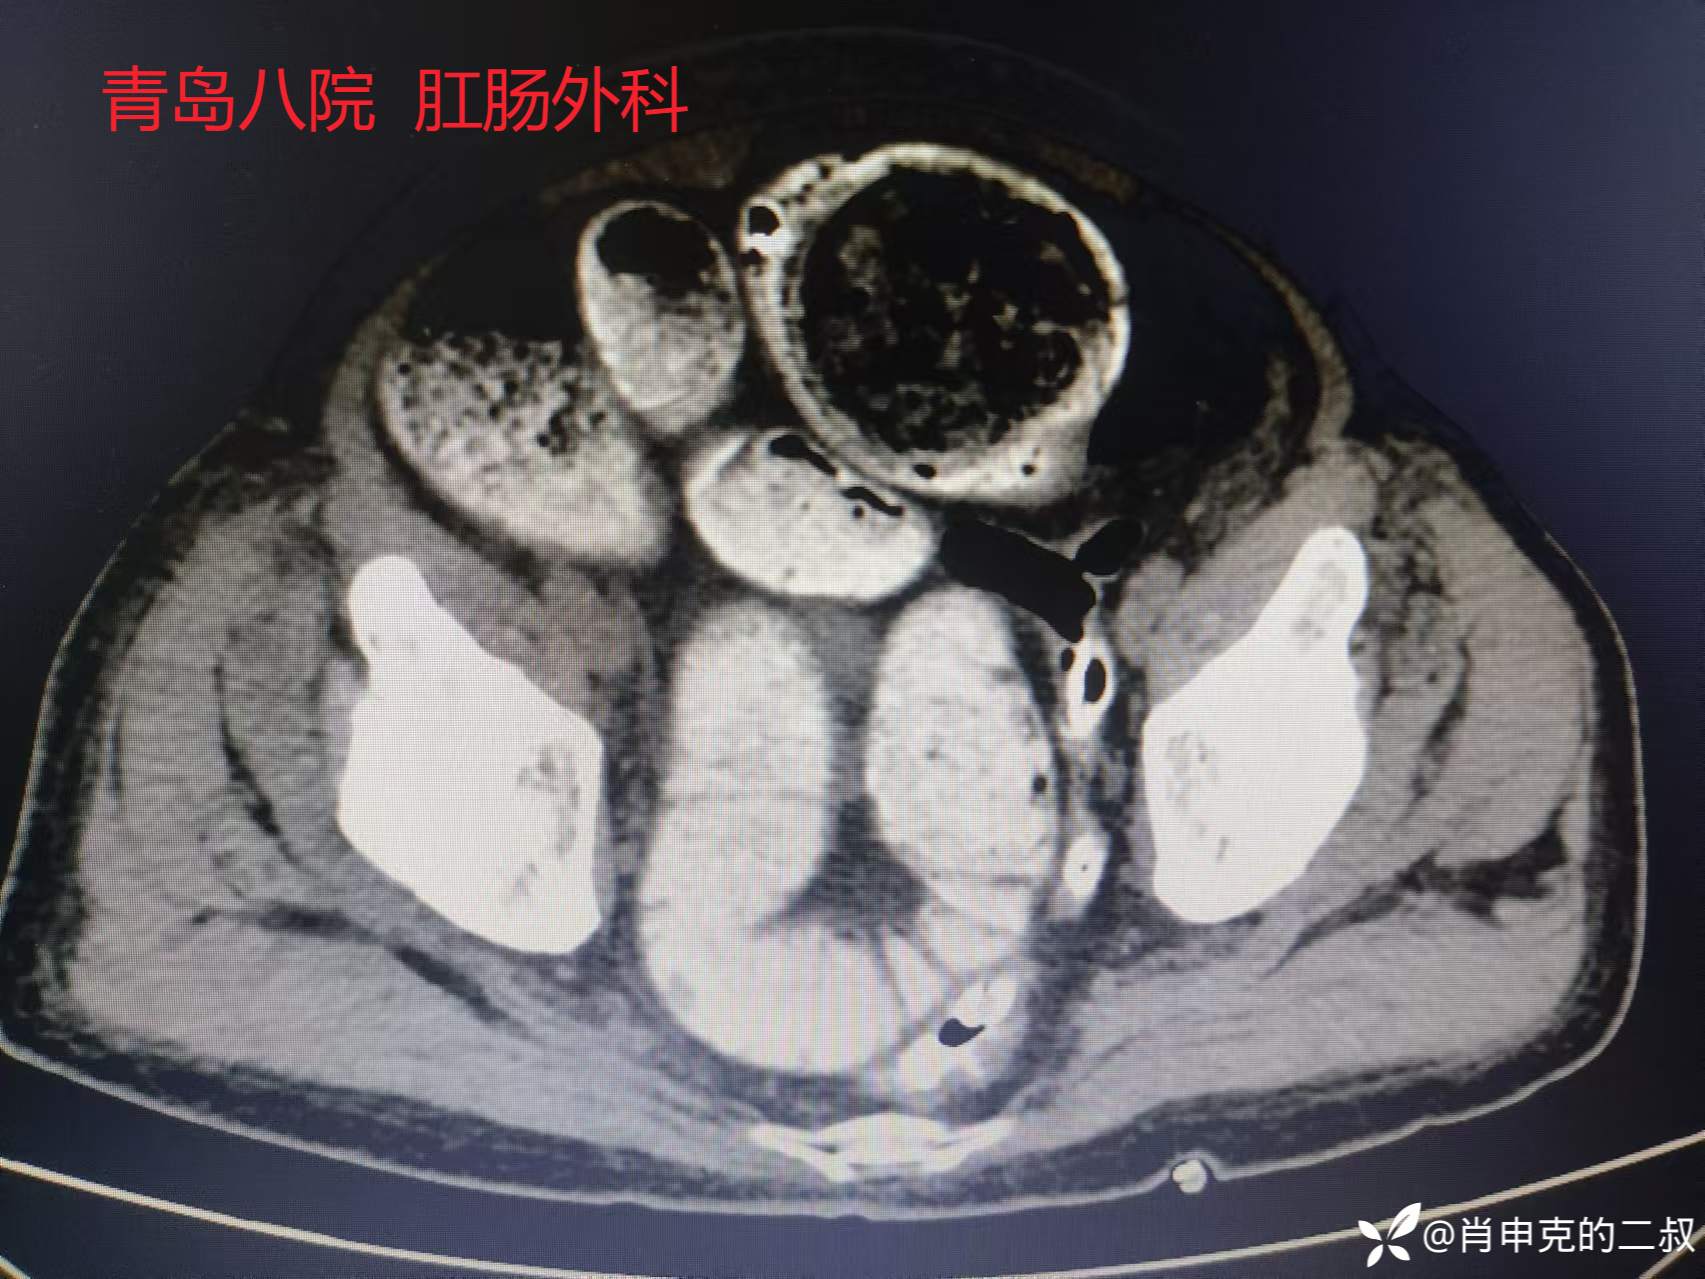

入院后急诊行腹部CT检查:可见结肠、直肠扩张明显。

见如此腹部CT,当日与患者行内镜下减压治疗。